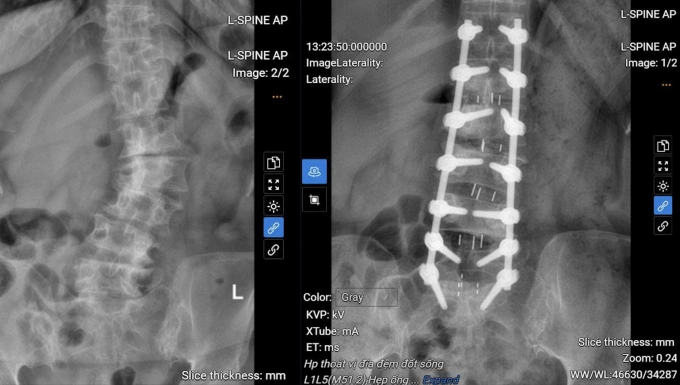

Cột sống người bệnh trước (trái) và sau phẫu thuật. Ảnh: Bệnh viện Đa khoa Tâm Anh